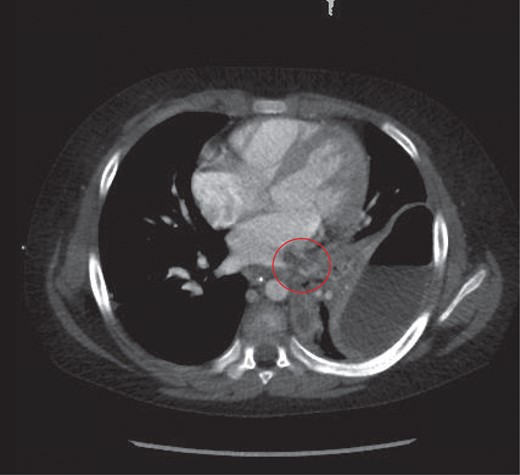

A further finding on the CT was of a large thrombus within the left pulmonary vein extending into the left atrium and a segmental left lower lobar pulmonary embolus (Fig. 3). The left hemidiaphragm was intact. The abdomen and pelvis showed no further source or complication of sepsis.

Thrombus noted in the left pulmonary vein extending into the left atrium.